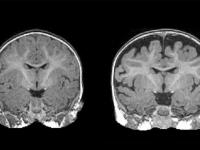

A día de hoy, el diagnóstico de los trastornos del espectro del autismo (TEA) solo se establece cuando el niño, ya sea a la edad de dos años o, incluso, de cuatro años, manifiesta de una forma patente los síntomas del comportamiento característicos del autismo, caso de un déficit en la comunicación, la dificultad para una correcta integración social, una dependencia exagerada de las rutinas, o una gran intolerancia ante los cambios o a la frustración.